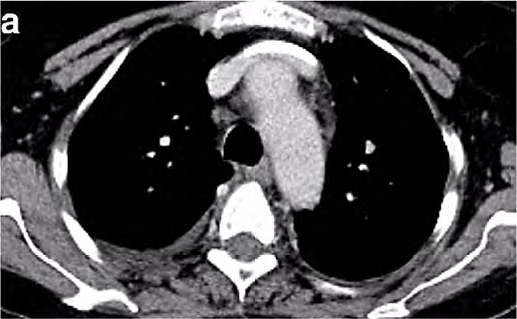

Um paciente de 62 anos de idade, tabagista ativo, cerca de 180 anos-maço, queixa-se de cansaço, tosse seca e perda de peso; por isso, procurou atendimento médico. O paciente referiu que pesava 100 kg e perdeu 10 kg. Realizou-se tomografia computadorizada de tórax, com evidência de lesão sólida de 2,1 cm em topografia de lobo inferior à direita, sólida, espiculada, com margens bem definidas e densidade de partes moles, assim como linfonodomegalia paratraqueal direita de 1,5 cm, paratraqueal esquerda de 1,2 cm e subcarinal de 2 cm. O paciente foi submetido a PET-CT de corpo inteiro, com evidência de hipercaptação de radiofármaco pela lesão (SUV 12) e pelo linfonodo representado na figura 2 a seguir.

Figura 1: TC de tórax sem contraste